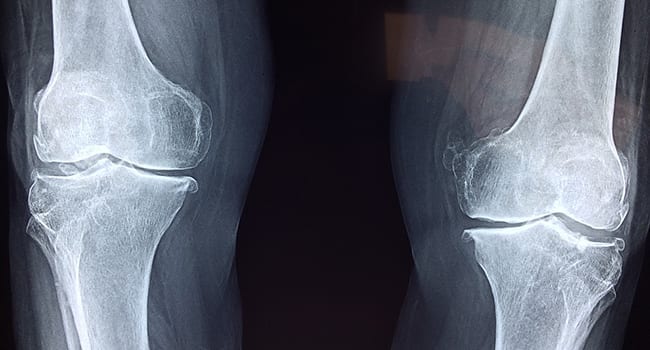

Like the PCL, the ACL runs deep inside the knee joint and provides more forward-backward stability of the joint by keeping the shin bone from gliding too far forward past the thigh bone. But unlike the PCL, the ACL also contributes to rotational stability of the knee joint.

In these cases, Le said surgery is always on the table but not always a given. She said some things to consider include what activities you want to get back to and the prevalence of any pre-existing conditions like osteoarthritis. In patients with knee osteoarthritis, evidence suggests surgery can exacerbate symptoms linked to this joint disease.